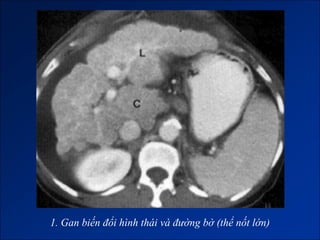

Hình ảnh trên CLVT

- Giai đoạn muộn:

+ Gan biến đổi hình thái và đường bờ.

+ Dấu hiệu tăng ALTMC.

+ Dấu hiệu khác:

Dịch ascite – Lách to – Dày thành TM.

Nốt tân tạo.

Biến chứng (HCC).

1. Gan biến đổi hình thái và đường bờ

1. Gan biến đổi hình thái và đường bờ (thể nốt lớn)